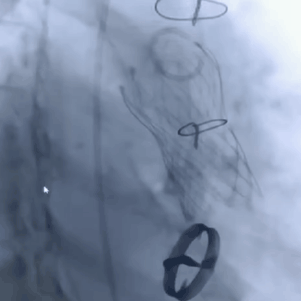

瓣膜释放后造影评估

术后压差从46mmHg降至6mmHg

术后超声心动图提示:主动脉瓣人工瓣膜前向1.9m/s,平均垮瓣压差约6mmHg,微量反流,左室壁博幅正常范围,心包未见积液,手术效果良好。